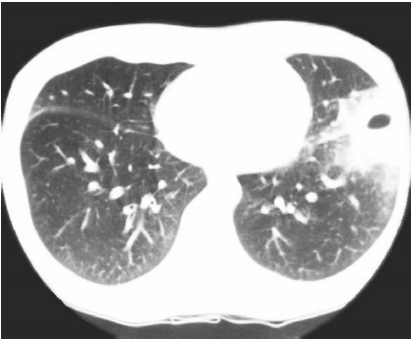

Considere a imagem, a seguir:

Fonte: http://rle.dainf.ct.utfpr.edu.br/hipermidia/images/documentos/Patologias_toracicas_achados_de_imagem.pdf

A figura, acima, representa um exame por tomografia computadorizada demonstrando consolidação do espaço aéreo com lesão escavada de permeio em língula, o que indica: